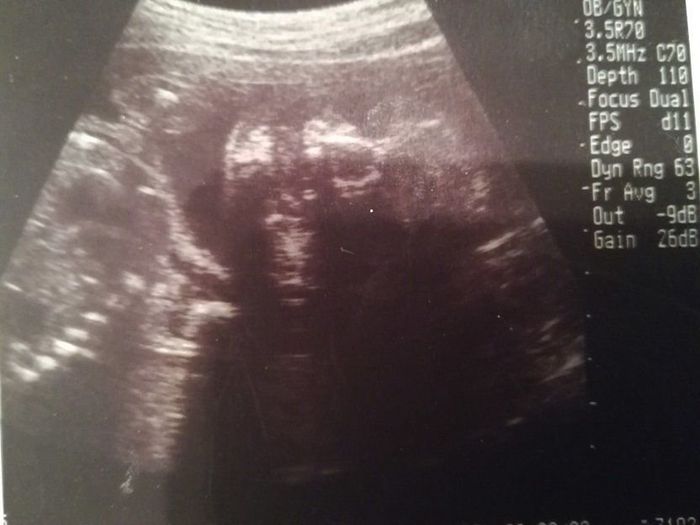

妊娠12週目のエコー写真

上の二つの画像は、同じ日に撮ってもらったもの。人の形になっている赤ちゃんの姿を確認して、体に衝撃が走りました。エコー画像上で、小さい体をモゾモゾと動かしている様子も見られて、本当にかわいらしく、感動して少し目が潤んでしまいました。人の姿として確認できる画像でしたので、夫に見せても、実家に帰省して両親に見せても、みんな「おぉー!」と喜びの声を上げていました。